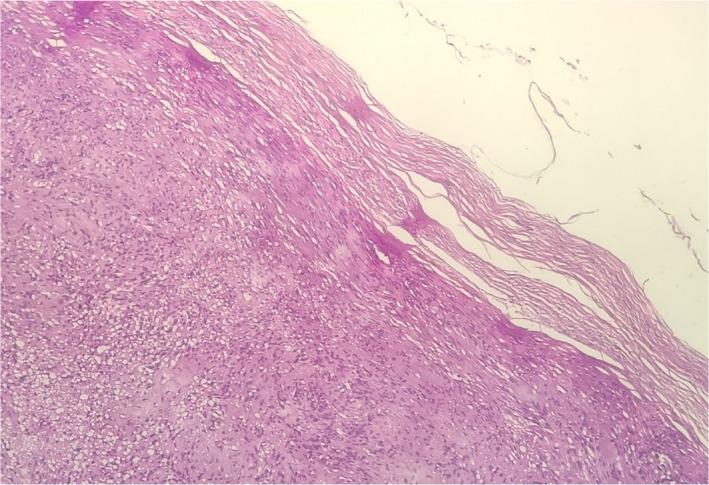

鼻侧壁神经鞘瘤:一例报告。

Schwannoma of the lateral nasal wall: A case report.

Nasal schwannomas account for about 4% of head and neck schwannomas. We report a rare case of lateral nasal wall schwannoma presenting as a nasal mass in a 70-year-old man.

摘要

鼻神经鞘瘤约占头颈部神经鞘瘤的4%。我们报告一例罕见的外侧鼻壁神经鞘瘤病例,该病例表现为一名70岁男性的鼻腔肿物。